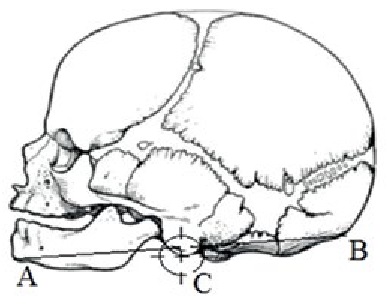

В работе определяли топографо-анатомические взаимоотношения нижней челюсти и уха плода, расположение в разные возрастные периоды центральной части (точка С) ушной раковины относительно нижней челюсти (АВ – линия, соединяющая точку гнатион и наружный затылочный выступ). Ушная раковина рассматривалась как фигура, приближенная к окружности. Внутри окружности были проведены две перпендикулярные линии, точка пересечения которых являлась центром симметрии геометрической фигуры и использовалась в качестве условного центра ушной раковины (обозначенного на рисунках как точка С).

В работе использованы краниометрические точки: «наружный затылочный выступ», «подбородочный выступ», на которые мы ориентировались при оценке перемещения ушной раковины.

Ушная раковина в течение промежуточного плодного периода при росте плода в норме смещается вверх относительно нижней челюсти. В начале изучаемого периода ушная раковина расположена чуть ниже угла нижней челюсти. Ее центральная часть (С) находится ниже линии (АВ), соединяющей точку гнатион и наружный затылочный выступ. Перпендикуляр от условного центра ушной раковины до линии АВ составляет половина диаметра ушной раковины и в среднем равен 3,7±1,1 мм (таблица 1).

Во второй возрастной группе ушная раковина расположена на уровне ветви и угла нижней челюсти. Ее условный центр (С) находится ниже линии АВ и составляет ¼ диаметра ушной раковины в среднем 3,1±0,8 мм (таблица 1).

К концу промежуточного плодного периода ушная раковина смещается до уровня отростков нижней челюсти выше вырезки. Ее центральная часть находится выше линии АВ, перпендикуляр от точки С до линии АВ равен 6,1±1,4 мм (таблица 1).

Топографические взаимоотношения нижней челюсти и ушной раковины изучались методом макромикроскопического препарирования. У плодов в промежуточном плодном периоде онтогенеза на уровне ветви и угла нижней челюсти расположена ушная раковина не выше линии, соединяющей наиболее выступающую точку тела нижней челюсти и затылочный бугор. Сформированы и определяются элементы строения ушной раковины: завиток, противозавиток, козелок, противокозелок, мочка. За козелком открывается отверстие наружного слухового прохода (рисунок 2). Возможно определение количественных характеристик данных элементов уха.

Рисунок 2. Макропрепарат. Фрагмент плодного материала. Возраст 19 недель. Пол мужской. 1 – тело нижней челюсти; 2 – угол нижней челюсти; 3 – венечный отросток; 4 – мыщелковый отросток; 5 – ушная раковина.

Figure 2. Macropreparation. A fragment of fetal material. Age 19 weeks, male. 1 – body of the lower jaw; 2 – angle of the lower jaw; 3 – coronoid process; 4 – condylar process; 5 – auricle.